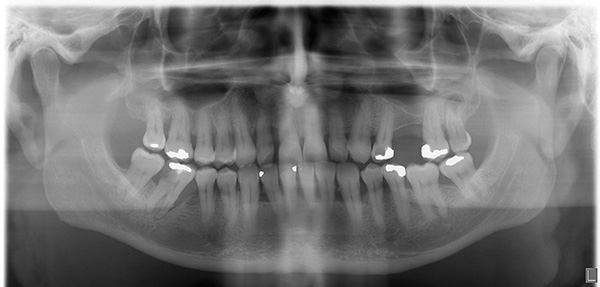

- ortopantomogramma: un'immagine panoramica che copre una o entrambe le dentature;

Ecco come appare un ortopantomogramma: